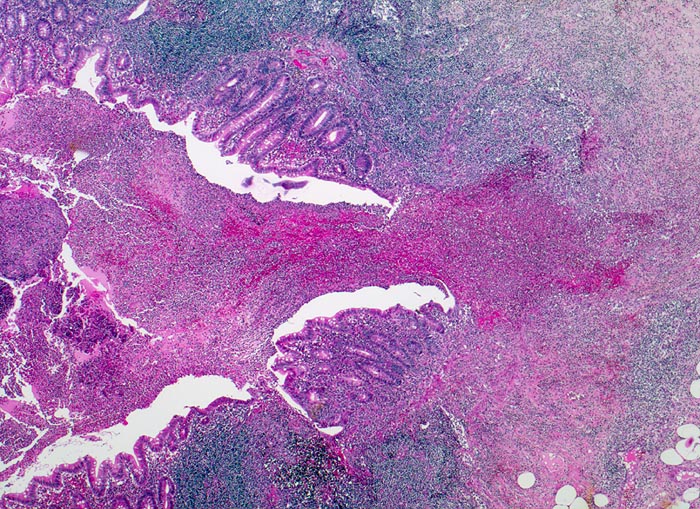

• Fokale Ulzeration der Appendixschleimhaut.

• Diffuse Durchsetzung der Appendixwand mit neutrophilen Granulozyten (phlegmonöse Entzündung).

• Fibrinauflagerungen auf der Serosa durchmischt mit neutrophilen Granulozyten (fibrinös eitrige Peritonitis). Das sollte der Kliniker dem Pathologen mitteilen: